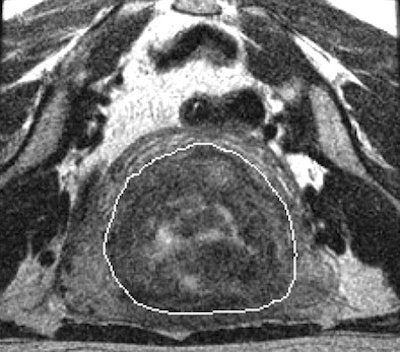

| Above, T2-weighted axial MR image of a hypointense fibroid in a 46-year-old patient before MR-guided focused ultrasound surgery. Below, T1-weighted gadolinium-enhanced axial MR image of the same fibroid immediately after treatment. |